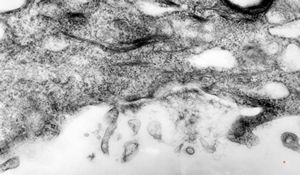

M, 17y. | Fabry disease

M, 17y. | Fabry disease

M, 17y. | Fabry disease

M, 17y. | Fabry disease